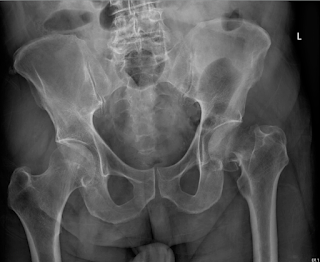

Neck of Femur Fracture

An old woman falls inside a bathroom as her feet slipped off. Her X-ray is shown as below.

https://kwaktalk.org/ortho/2020/12/27/hip-fractures